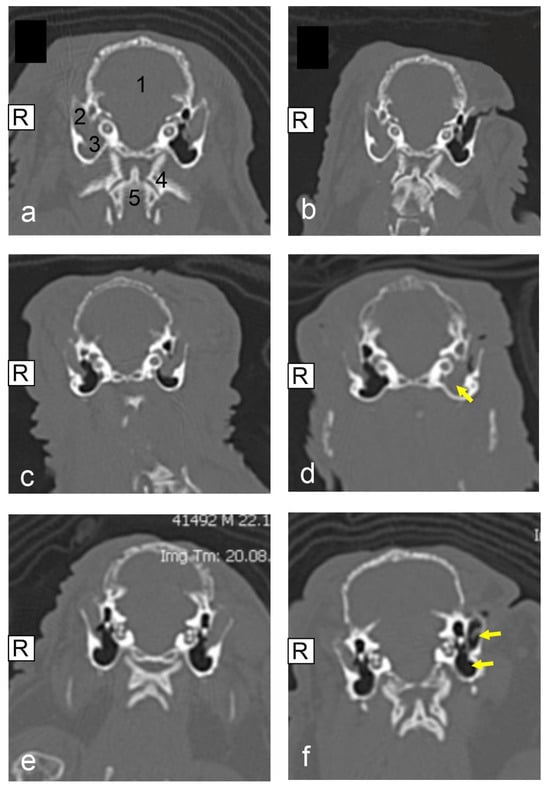

Relating to a total of 18 pet rabbits with one surgically treated ear, four of those were diagnosed with grade I, and nine pet rabbits with grade II for the external ear canal. In none of these cases was concomitant otitis media identified on the same ear. Two cases had grade III for the external ear canal and both pet rabbits also showed grade I otitis media on the respective ear. A total of three pet rabbits were diagnosed with grade IV for the external ear canal. One of these pet rabbits was also diagnosed with grade I otitis media on the same ear. Both ears were reviewed and categorized for another seven pet rabbits. See Figure 1 for exemplary CT images.

3.5. CT Results Post Surgery

Repeat CT imaging was performed in 14 of the 25 pet rabbits. The time of repeat CT imaging varied between 30 and 762 days post-surgery. One pet rabbit was presented for two follow-up CT examinations. The results of the 14 pet rabbits that received repeat CT imaging are presented in Table 1. In summary, 8 of these 14 pet rabbits showed an improved or partially improved ear grading in the post-operative images based on the status of soft tissue filling. Four of the eight pet rabbits exhibited an improvement in one grade for the external ear canal. Another four pet rabbits showed an improvement of two grades for the external ear canal. Four pet rabbits identified on post-operative CT imaging demonstrated no apparent change to their ear condition. Finally, 2 of the 14 pet rabbits showed a worsening of the soft tissue filling of their ears. In 4 of the 25 cases, the ipsilateral middle ear was included in the disease process. The degree of soft tissue filling of the middle ear remained unchanged in two cases (pet rabbits no. 4 and no. 11). In two cases, the degree of soft tissue filling of the middle ear worsened at the time of the repeated CT images (pet rabbits no. 18 and no. 19). See Figure 1 for exemplary CT images.

Figure 1. Computed tomographic (CT) image (native, transversal plane, bone window) (af): veterinary clinic Posthausen, Germany); (a,b): pet rabbit no. 14, (a): prior to lateral ear canal ablation (LECA) surgery on the left ear, (1) cranium, (2) external ear canal, (3) middle ear, (4) first cervical vertebra, and (5) second cervical vertebra; (b): 365 days after LECA surgery on the left ear, improved ear status, external ear nearly completely filled with air; (c,d): pet rabbit no. 19, (c): prior to LECA surgery on the left ear, (d): 240 days after LECA surgery, complete soft tissue filling of the middle ear; (e,f): pet rabbit no. 20, (e): prior to LECA surgery on the left ear, (f): 365 days after LECA surgery, improved ear status, external ear nearly completely filled with air.